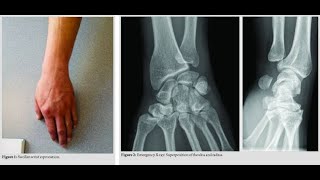

Distal Radioulnar Joint Druj Dislocation Explained

Distal Radioulnar Joint Druj Disruption Kasus...